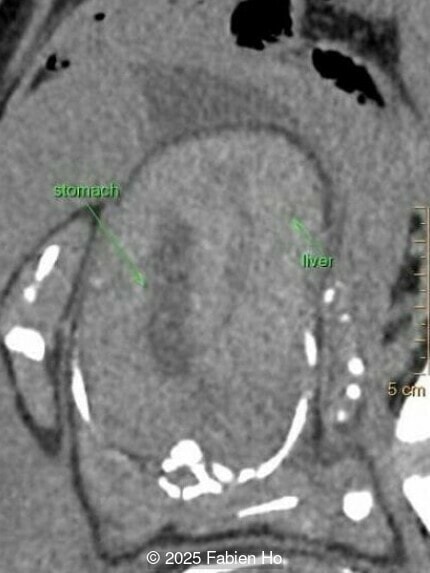

Coronal image of the thorax and abdomen

Image 5 Coronal image of the thorax and abdomen

Our prenatal ultrasound revealed a male fetus with megabladder, dilation of both ureter and kidneys, and thinned kidney parenchyma consistent with Lower Urinary Tract Obstruction (LUTO).  Additional findings suspected on ultrasound and confirmed on computed tomography included:

• Short long bones (<1st percentile), normal mineralization, and no sign of lethal chondrodysplasia

• Evidence of Potter's sequence due to the lower urinary tract obstruction with small thorax compared to the abdomen, hyperextended neck, and pes varus.

At 36 weeks gestation, the abdominal findings were unchanged however, the bones appeared short (<1st percentile) and the spine had an unusual appearance, therefore a computed tomography was performed at 37 weeks gestation.